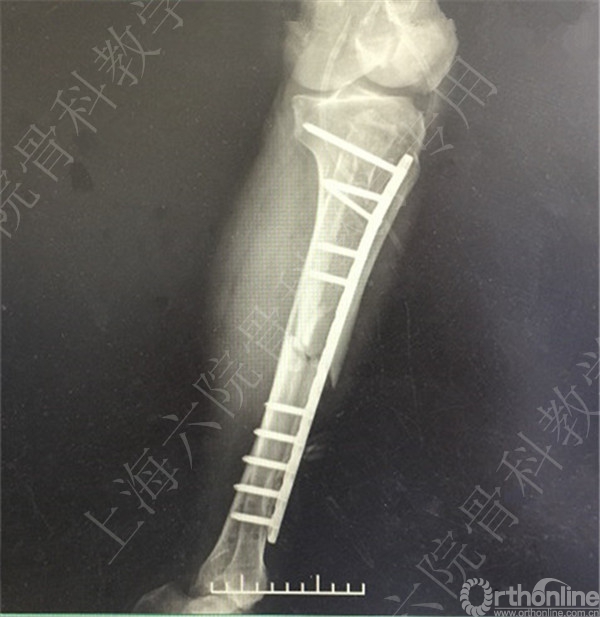

患者择期行左胫骨切开复位内固定术+髂骨异体骨植骨。

术后X线摄片示:骨折对位对线可,内固定牢靠,左胫骨对线可。

医方第一次跟换内固定术中,未纠正左胫骨立线,骨折对位对线差,未纠正成角,导致术后内固定失效,骨折成角变大。医方存在手术方式不当,手术操作不当,术后并发症观察、处理不当,对疾病评估不足,告知缺陷等过失。